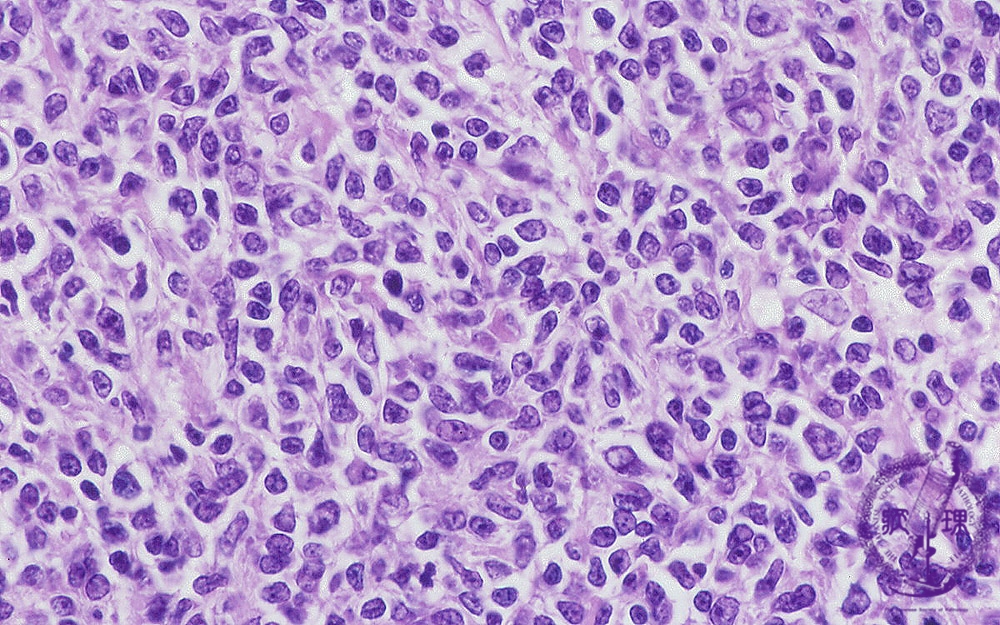

- ★(5)Follicular lymphoma

Microscopic image (H&E high power view): Nuclei of neoplastic lymphocytes are larger than those of mature lymphocytes (arrow No.1), but smaller than those of histiocytes. Some of the smaller tumor cells are called cleaved cells because their nuclei have irregular, notched borders (arrow No.2). Admixed centroblasts (arrow No.3) are larger tumor cells with prominent large nucleoli. The germinal center growth pattern is relatively monotonous in contrast to the heterologous appearance seen in non-neoplastic, reactive areas.